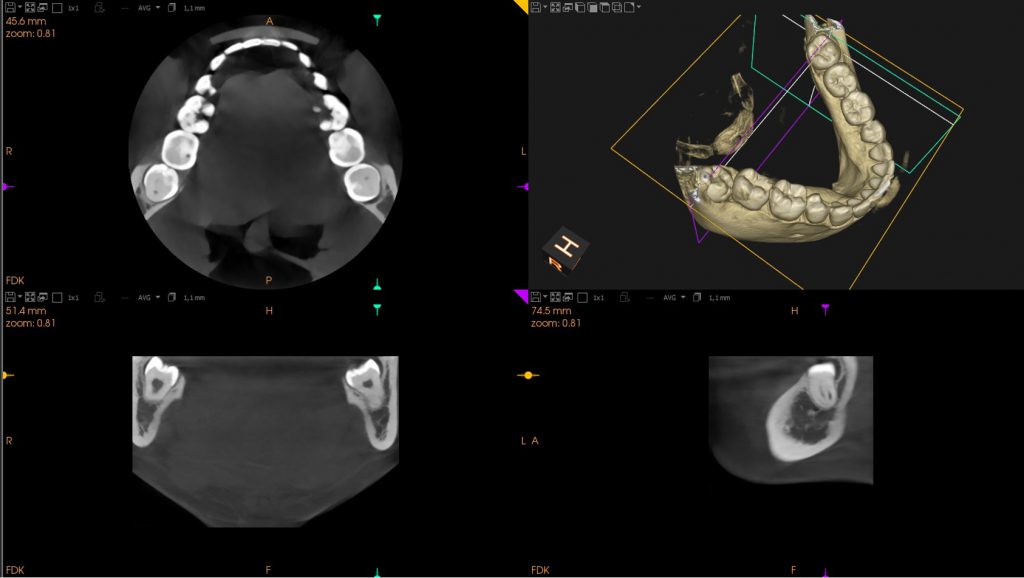

- Pueden mantenerse ocultos dentro de las encías. Si no pueden salir con normalidad, quedan atrapadas en la mandíbula. Esto, puede dar lugar a infecciones o incluso un quiste que, puede repercutir en las raíces de otros dientes o el hueso de soporte.

- Mal posicionamiento: cuando no salen rectos, pueden estar torcidos o inclinados dentro del hueso de la encía y provocan dolor.

- Quistes: la causa de la aparición es que la muela del juicio no puede salir, se forma un saco que la envuelve y se llena de líquido. El quiste crece y daña las muelas adyacentes, el hueso circundante y los nervios. Si este no es tratado, puede ocasionar daños mayores.